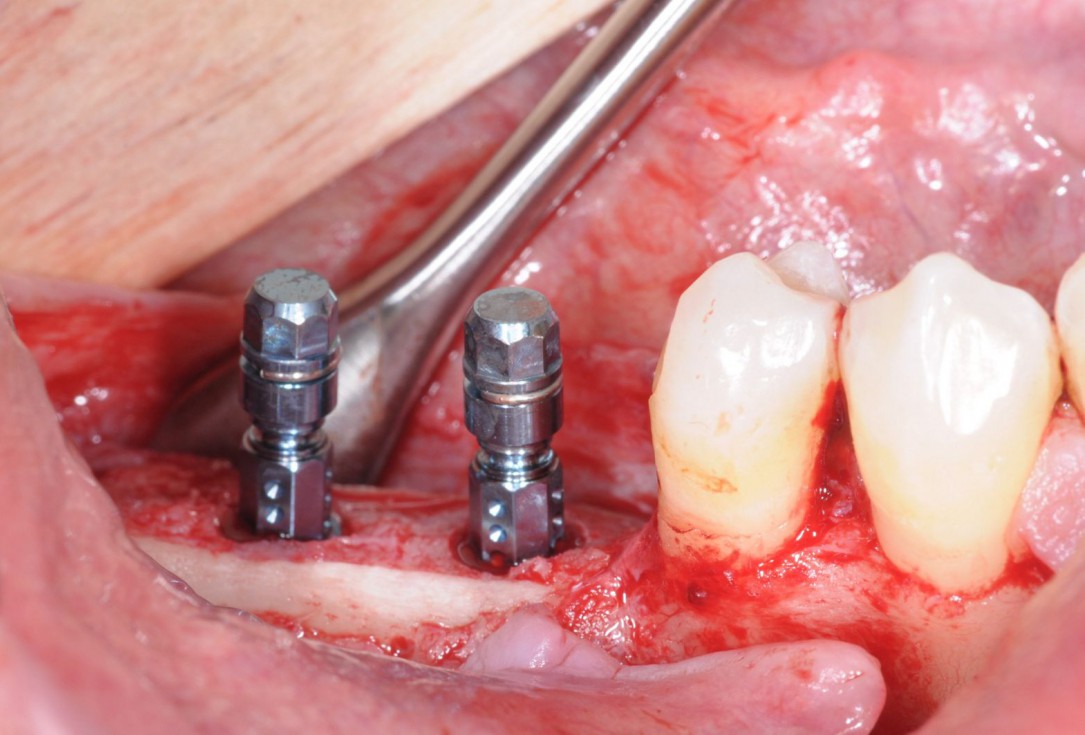

18/28 - Implantation of two Straumann BLT implants into the augmented boneThree-dimensional augmentation with maxgraft® cortico - Dr. R. Würdinger